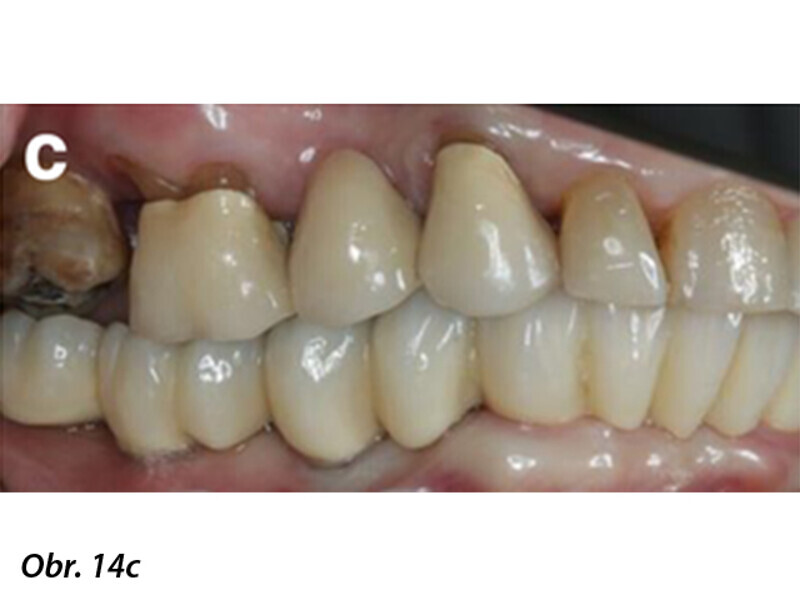

Počítačem asistované, šablonou se řídící okamžité zavedení a zatížení implantátu v dolní čelisti